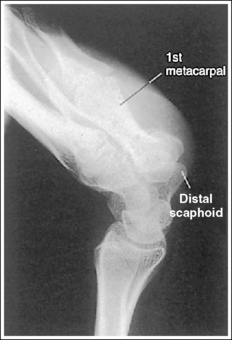

The wrist is in a lateral projection. The anterior aspect of the distal scaphoid and pisiform are aligned, and the radius and ulna are superimposed.

• A lateral projection of the wrist is accomplished by flexing the elbow 90 degrees and abducting the humerus until it is parallel with the IR, placing the entire arm on the same horizontal plane. Rotate the wrist into a lateral projection with its ulnar (medial) aspect against the IR (Figure 4-38). To ensure a true lateral projection, place the palmar aspect of your thumb and forefinger against the anterior and posterior aspects, respectively, of the patient's wrist joint, as shown in Figure 4-39. Adjust wrist rotation until your thumb and finger are aligned perpendicular to the IR.

• Detecting wrist rotation. The relationship between the pisiform and distal aspect of the scaphoid can best be used to discern whether a lateral wrist projection has been obtained. On a lateral projection, these two carpals should be superimposed, with their anterior aspects aligned. When the wrist is rotated, the anteroposterior relationship between the distal scaphoid and pisiform changes, and the pronator fat stripe is obscured. If the anterior aspect of the distal scaphoid is positioned posterior to the anterior aspect of the pisiform, the patient's wrist was externally rotated (see Image 45). If the anterior aspect of the distal scaphoid is positioned anterior to the anterior aspect of the pisiform, the patient's wrist was internally rotated (see Images 46 and 47). A second method of determining how to reposition a rotated lateral wrist projection uses the radius and ulna. The ulna is positioned anterior to the radius when the wrist was externally rotated and the ulna is positioned posterior to the radius when the wrist was internally rotated. Because the exact amount of superimposition of the radius and ulna depends on the position of the humerus, and their poor positioning is not as sensitive, you should always view the pisiform and distal scaphoid relationship when determining whether the wrist is in a lateral projection.

The carpal bones do not indicate radial or ulnar deviation. The distal aspect of the distal scaphoid is aligned with the distal aspect of the pisiform.

• To obtain a neutral lateral wrist projection, align the long axes of the third metacarpal and the midforearm parallel with the IR. When the proximal forearm is higher or lower than the distal forearm, the wrist is radial-deviated or ulnar-deviated, respectively. In radial and ulnar deviation the distal scaphoid moves but the pisiform's position remains relatively unchanged. Radial deviation of the wrist forces the distal scaphoid to move anteriorly and proximally (Figure 4-40), causing the distal aspect of the distal scaphoid to be positioned proximal to the distal aspect of the pisiform (see Image 49). Ulnar deviation shifts the distal scaphoid posteriorly and distally (see Figure 4-40), causing the distal aspect of the distal scaphoid to be positioned distal to the distal aspect of the pisiform (see Image 50). The degree of pisiform and distal scaphoid separation is usually very small, because you would be unlikely to position a patient in maximum wrist deviation without being aware of the positioning error. To obtain optimal lateral wrist projections, however, you must learn to eliminate even small degrees of deviation.

The long axis of the first metacarpal is aligned parallel with the forearm.

• If the long axis of the first metacarpal is positioned adjacent to the second metacarpal and aligned parallel with the forearm, the patient's wrist is placed in a neutral position.